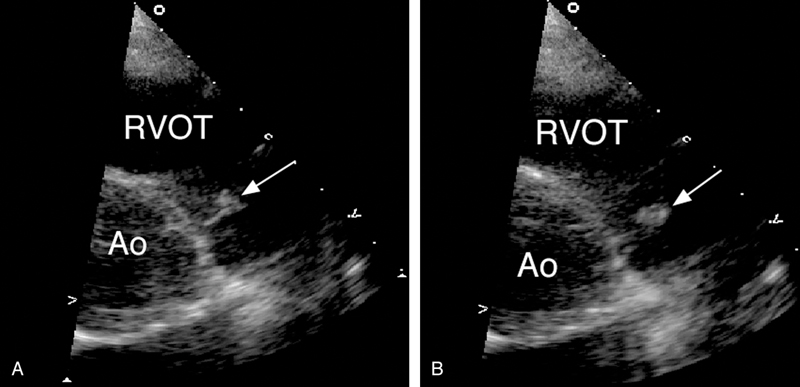

فحوصات تشخيصية لبعض امراض القلب والشرايين التاجية